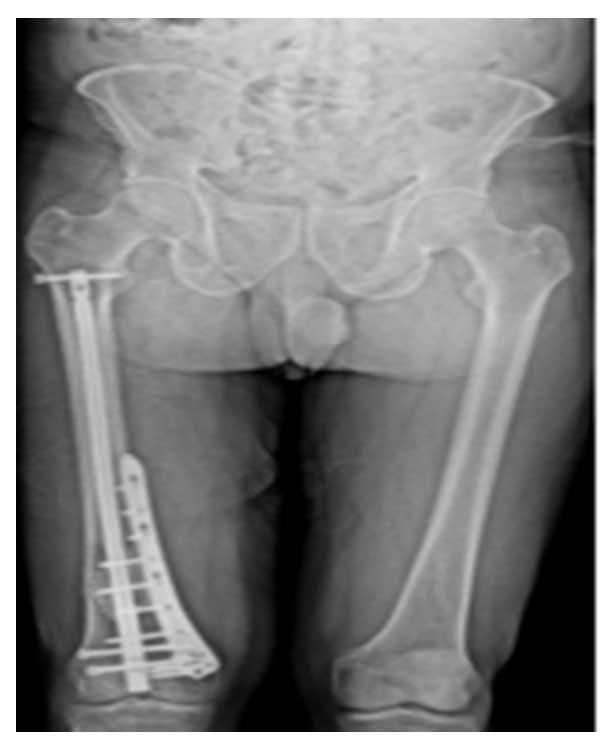

Ameliyat Sonrası: Röntgende tümörün temizlenmesi sonrası oluşan boşluğun kemik çimentosu ile doldurulması, içten çivi ve dıştan plak ile güçlendirilmesi görülmekte.